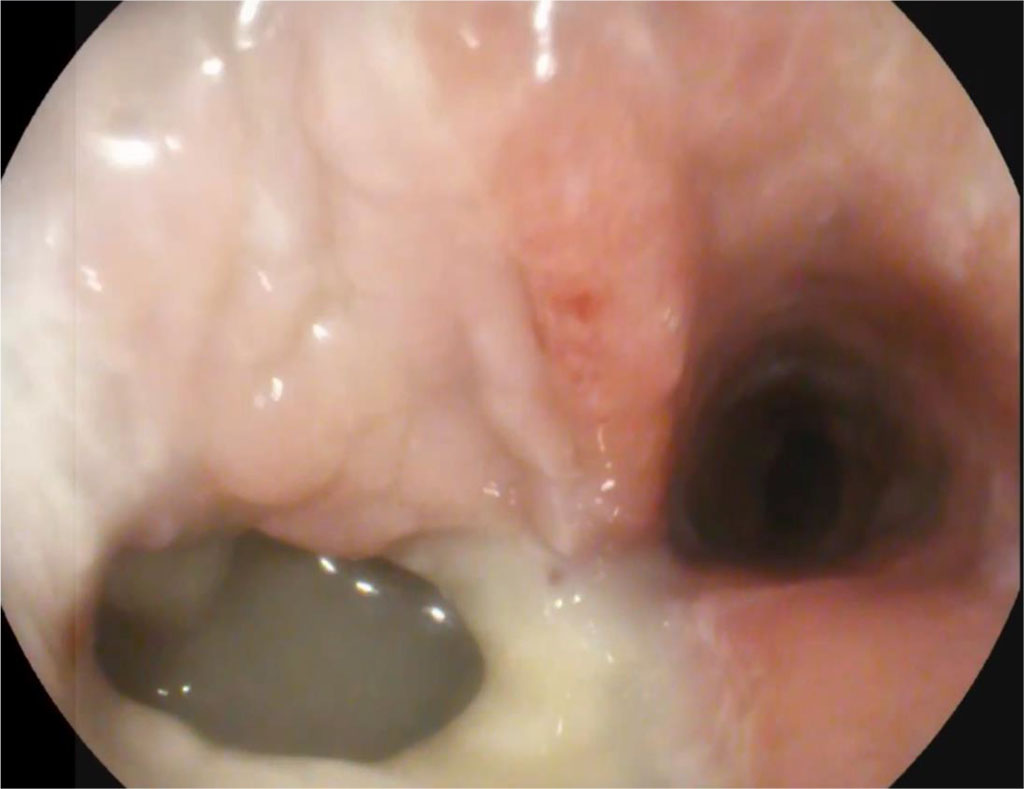

Since the pyloric part of the stomach was gaping, we refused to administer botulinum toxin, and we also did not perform stenting of the lumen in the area of the defect in the remnant stomach. At the same time, with ultrasound control, a drainage was placed in the abdominal cavity to the area of the defect. The patient was given totally parenteral nutrition and antibiotic therapy with broad-spectrum drugs. After 14 days, the drainage in the abdominal cavity stopped functioning. Fistulography showed that it was not in the abscess cavity; according to endoscopic fistulography, hermetic sealing was achieved.

Day 21, after endoscopic sanitation of the abscess cavity (once every 2 days) on an outpatient basis. Further, a significant decrease in size of the abscess cavity and fistula orifice was noted. Fig. 2.

Figure 2. 21 days after surgery (explanations in the text)